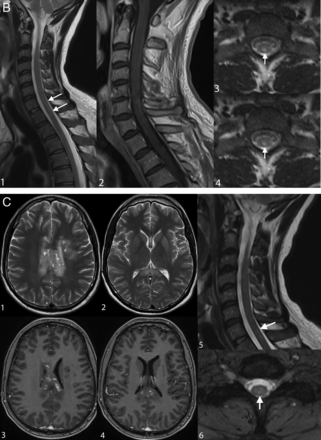

Reversible thoracic spinal cord lesion due to decompression sickness. MR imaging performed 24 hours after the diving accident shows a thoracic lesion appearing as a high signal on sagittal T2WI (A, white arrows). The lesion increases in size on the following day (B, white arrows) and subsequently disappears on day 13 (C). This evolution may also be consistent with edema.